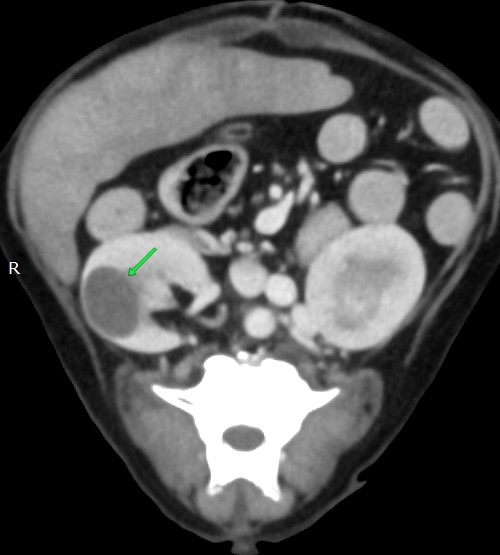

腫瘍を疑い手術ですので、術前にCT検査です

②左右に大きな腎臓に嚢胞

②腎不全になりやすいので点滴をしっかり